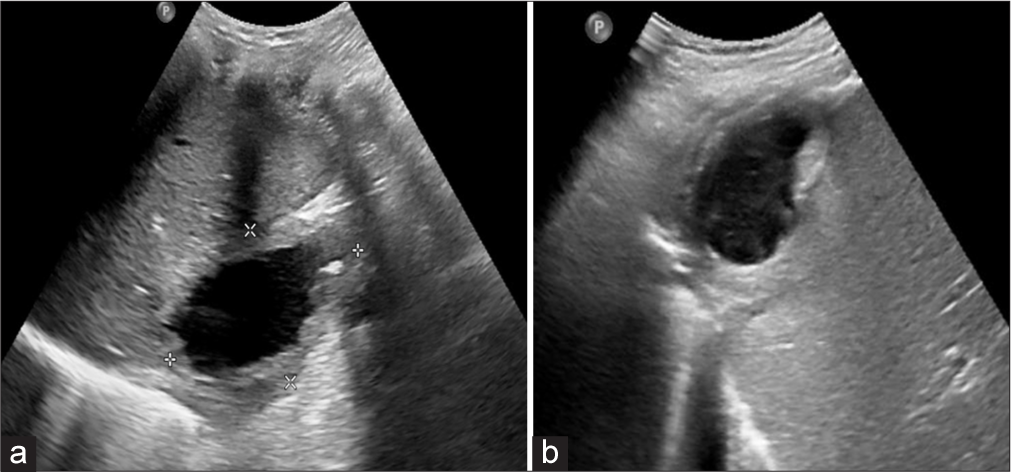

A 60-year-old male patient who had undergone a laparoscopic cholecystectomy 3 years ago for calculus cholecystitis presented with complaints of frequent right hypochondriac pain and fever. Ultrasound (USG) abdomen revealed a thick-walled collection in the subdiaphragmatic region near segment VI of the liver [Figure 1]. The patient had a similar history in the past for which an ultrasound guided aspiration was performed. A contrast-enhanced computed tomography (CECT) abdomen was advised in view of recurrent subdiaphragmatic abscess, which revealed a well-defined thick-walled peripherally enhancing hypodense collection in the right subdiaphragmatic region in contact with hepatic parenchyma of segment VI, with few tiny (2–3 mm) radiopaque foci noted in the wall of the collection [Figure 2]. Hence, based on imaging features, the possibility of dropped gallstones with recurrent abscess formation was considered. Laparoscopic-assisted abscess drainage with the extraction of retained gallstones was performed [Figure 3].

- (a) Ultrasound image showing irregular thick wall collection with small hyperechoic focus in the wall seen in subcapsular location of segment VII of liver. (b) Ultrasound image showing Irregular thick wall collection with echogenic content in subcapsular location of segment VII of liver.